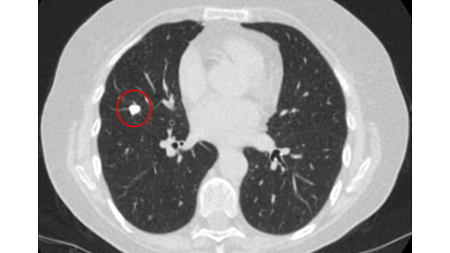

Tomografia computadorizada (TC) mostrando nódulo alongado periférico no lobo superior esquerdo, com captação de contraste e lado de alimentação e drenagem nítido, condizente com pequena malformação arteriovenosa

Do acervo de Dr. George Tsaknis, MD, PhD, FRCP (Londres), MRQA, MAcadMEd, PGCert; usado com permissão